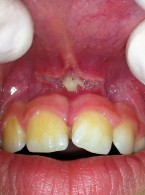

Pokrycie mnogich recesji dziąsłowych

metodą płata przesuniętego dokoronowo z wykorzystaniem przeszczepu podnabłonkowej tkanki łącznej i kolagenowego materiału ksenogennego po wcześniejszej rekonstrukcji połączenia szkliwno-cementowego - opis przypadku